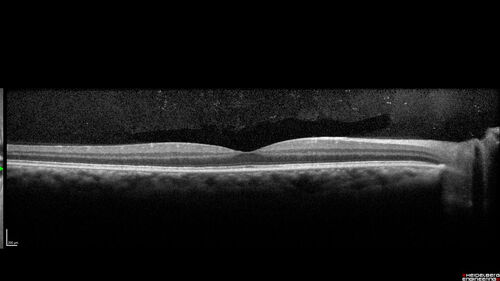

Syphilitic Chorioretinitis - 1 month post-treatment

41 year old man with vision loss for five days left eye. VA 20/32, 20/200